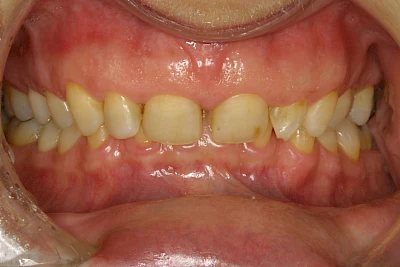

Über die Zeit können verschiedene Prozesse die Zahnhartsubstanzen aufzehren:

- Abnutzung durch Kauen (Abrasion) oder duch durch übermäßiges Knirschen bzw. Pressen (Attrition)

- Säurebedingte Auswaschung (Erosion)

- Knirschen bzw. Pressen und ungünstige Putztechnik (Druck): keilförmige Defekte

Auswaschung (Erosion) dagegen ist eine Verschleißerscheinung der Zähne aufgrund von immer wiederkehrenden Säureangriffen durch die Nahrung, verstärkt zum Beispiel durch den Genuss säurehaltiger Getränke oder Speisen. Auch bei Menschen mit einer Essstörung (z. B. Bulimie) können die Zähne durch die Magensäure ausgewaschen erscheinen.

Eine Sonderform sind sogenannte keilförmige Defekte im Bereich der Zahnhälse. Hier geht man davon aus, dass Knirschen und Pressen in Kombination mit falschen Putzgewohnheiten (zu hoher Putzdruck, Verwendung von Zahnpasta mit hohen Abrasionswerten) eine Rolle spielen.